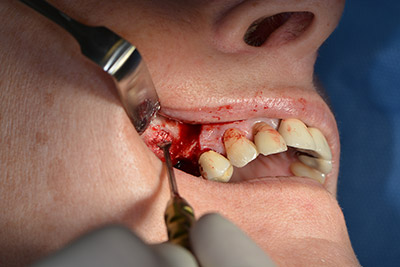

Последващите отвори се изборват с намалени обороти от 300 rpm. Implantmed демонстрира своя истински потенциал на този етап. Хирургичният протокол може да бъде зададен – различните позиции могат да бъдат лесно избрани чрез натискане на позиция “P” на педала (Фиг. 10 и 11).

Следващата програмирана позиция е поставянето на импланта и в нашата практика е предварително настроена на сила 32 Ncm (Фиг. 12).